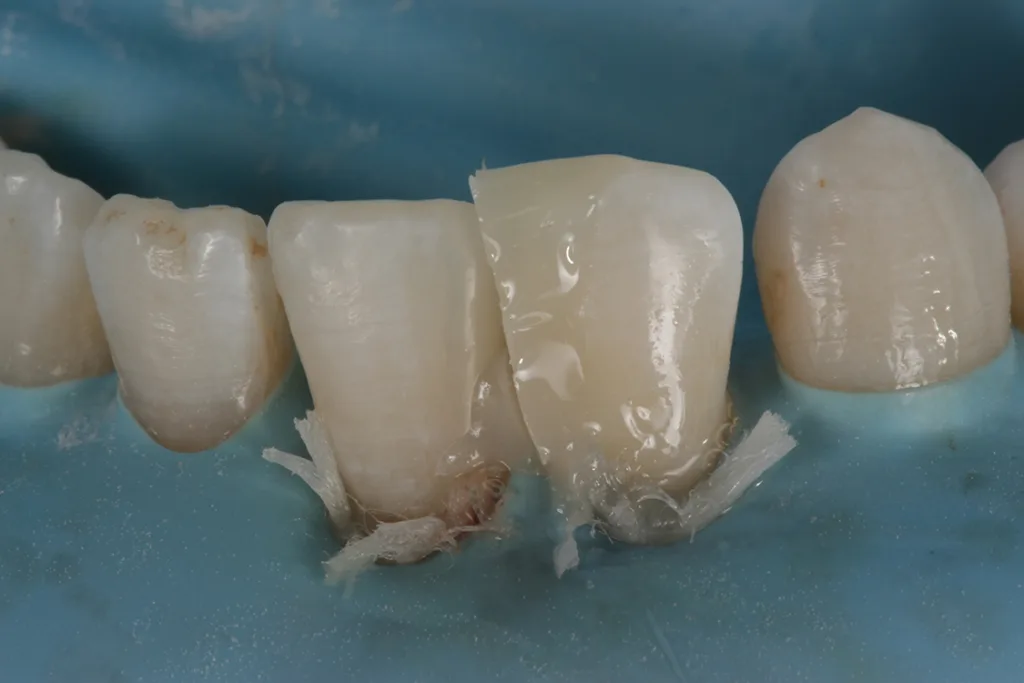

Nach Befundaufnahme und professioneller Zahnreinigung wurde ein CMD-Kurzscreening durchgeführt und ein Fotostatus erstellt. Ein intraorales Mock-up [2] wurde auf Wunsch der Patientin und aus Kostengründen nicht angefertigt. Definitive Versorgung Adhäsivrestaurationen mit Komposit an 31/32 zum Schluss des Diastema laterale (Abb. 3 bis 9).

Es zeigen sich postoperativ leichte Irritationen der Gingiva, die durch das Legen der Retraktionsfäden/Ligaturen entstanden sind und sich nach Abheilung und Reifung im Interdentalbereich noch adäquat ausformen werden, um somit einem ansprechenden dentogingivalen Erscheinungsbild zu entsprechen.